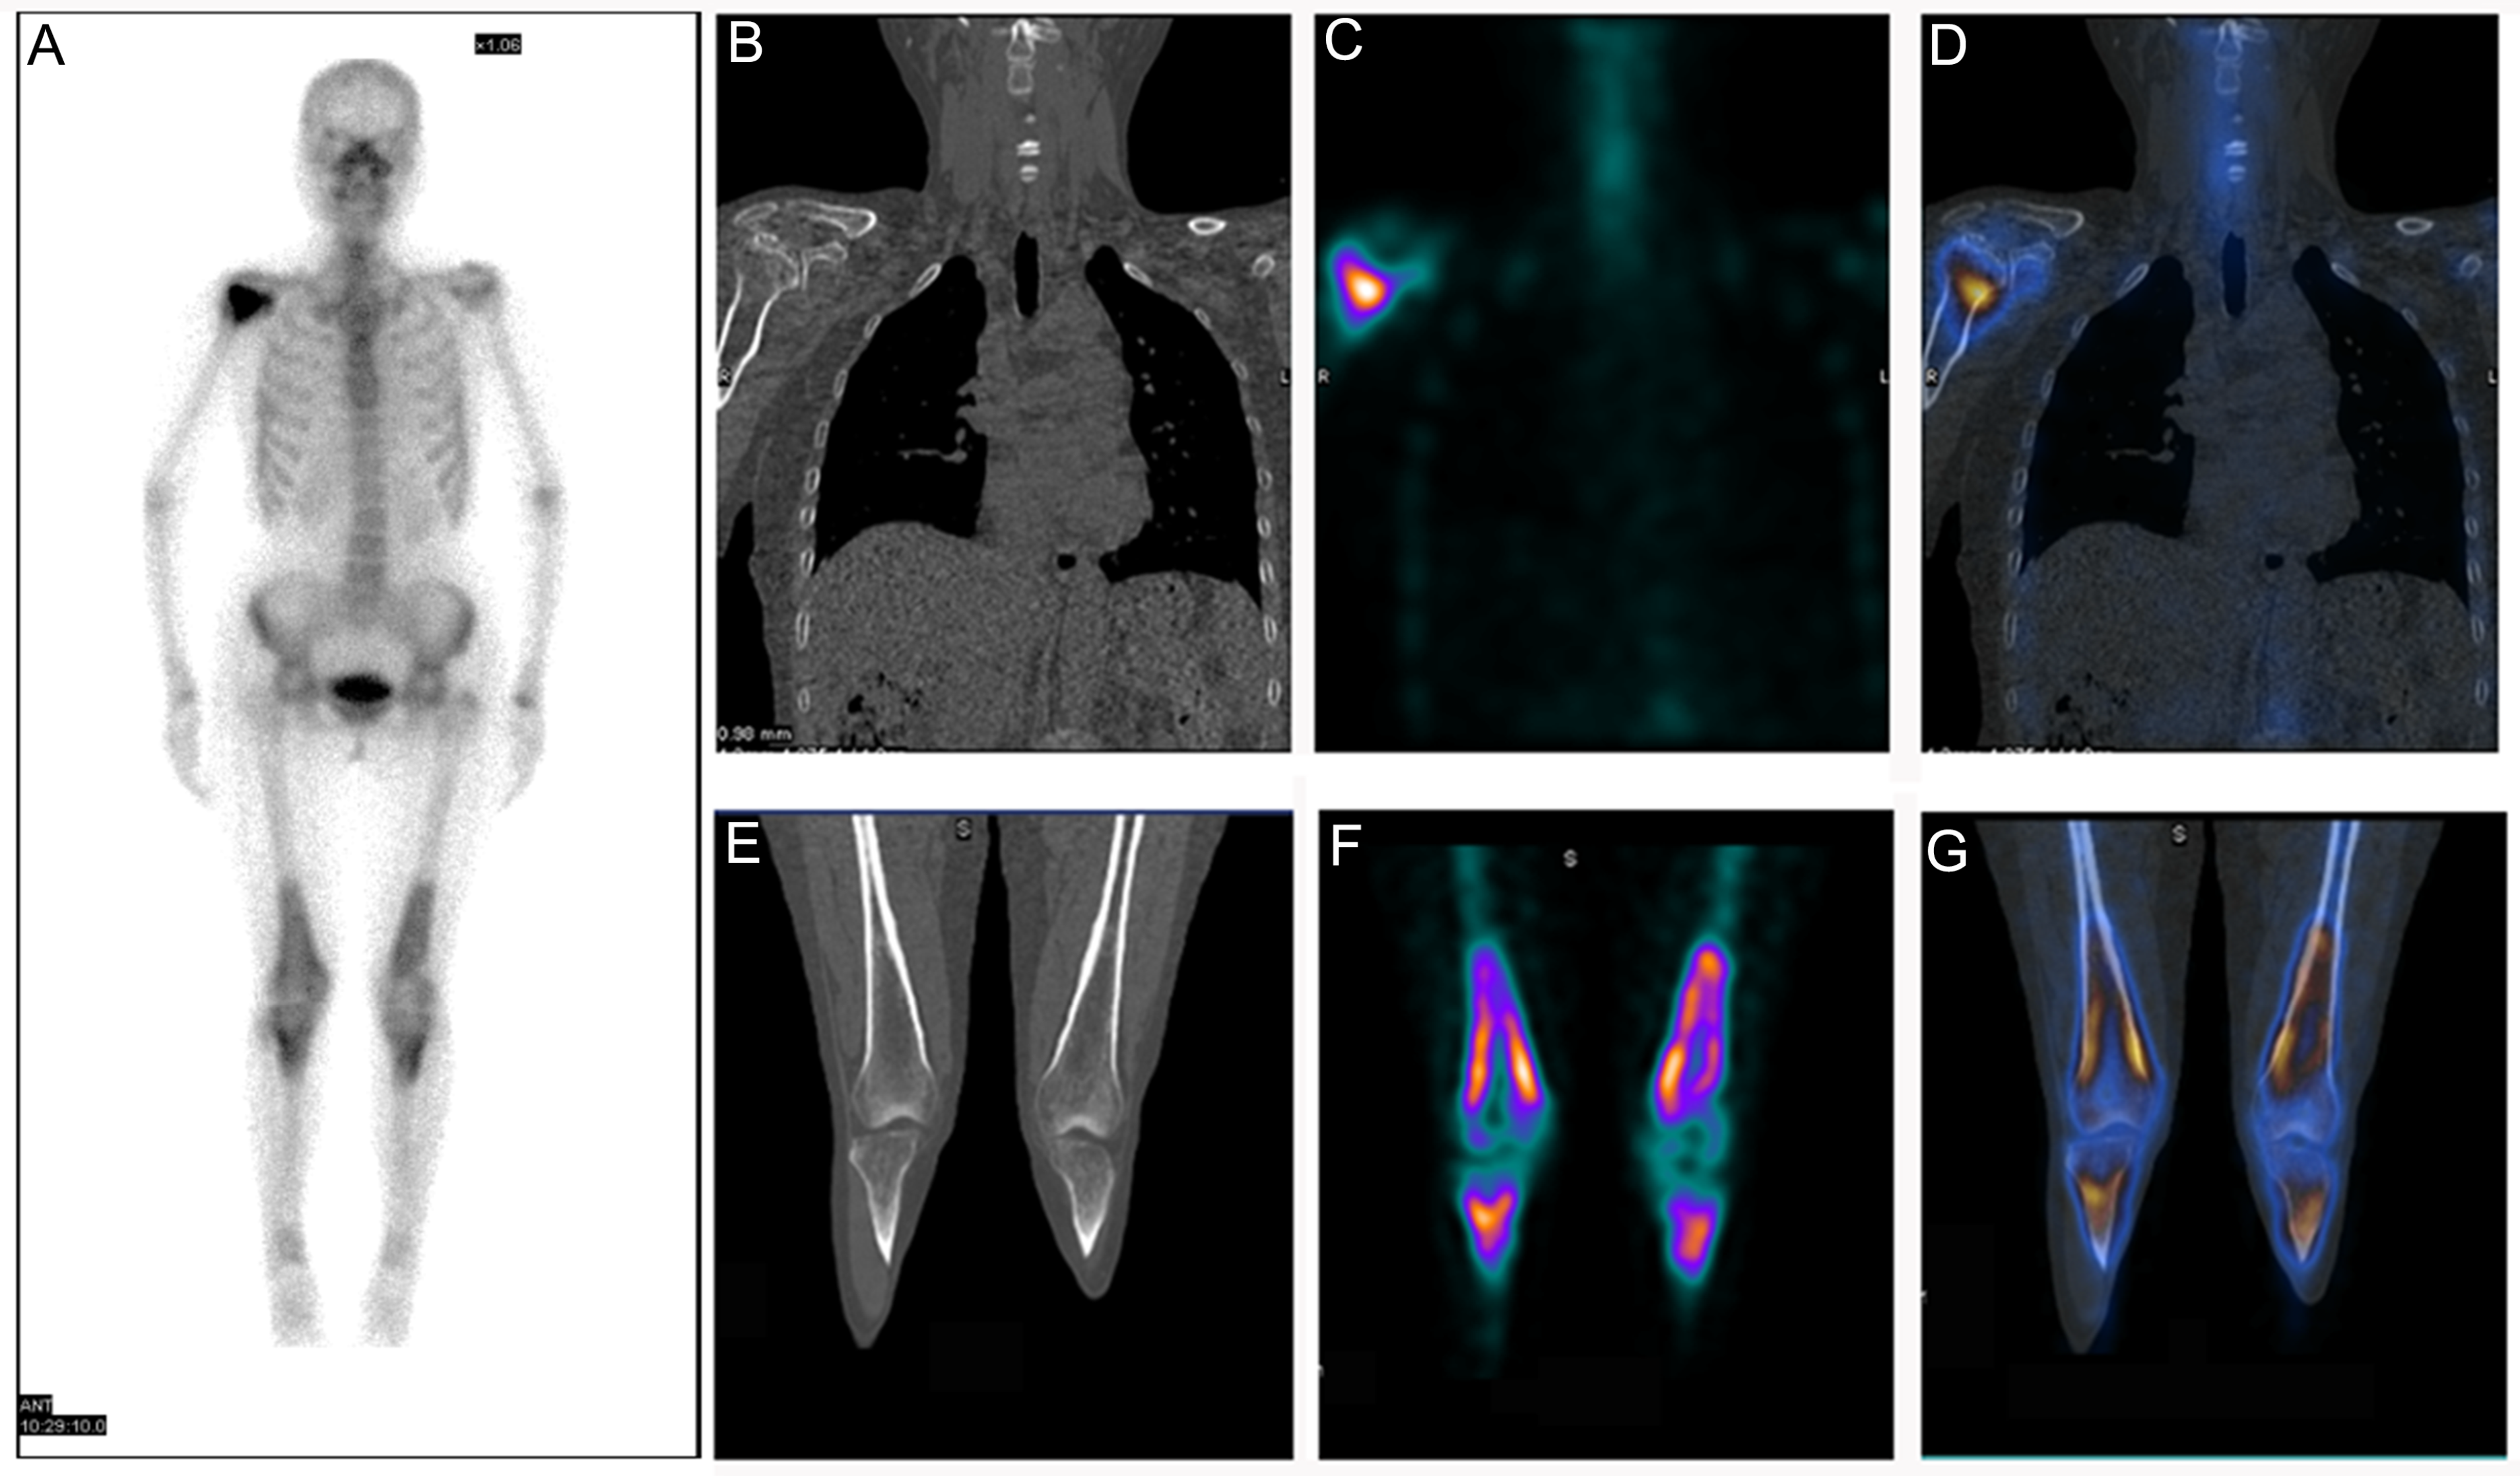

Diagnosis of Bone and Joint Disorders: Resnick, Donald, Differential Diagnosis of Rare Diseases Involving Bilateral,

Differential Diagnosis of Rare Diseases Involving Bilateral, Differential Diagnosis of Rare Diseases Involving Bilateral,

Differential Diagnosis of Rare Diseases Involving Bilateral, Lubbock Spine Institute Joint Disorders - Lubbock Spine,

Lubbock Spine Institute Joint Disorders - Lubbock Spine, Differential Diagnosis of Rare Diseases Involving Bilateral,